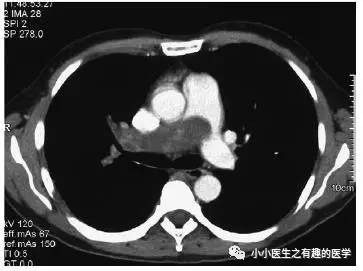

仔细看看,不对。

充盈缺损的地方,密度不均匀,并且,有强化,血栓里面没有血管,一般不会强化,所以,有可能是肿瘤。